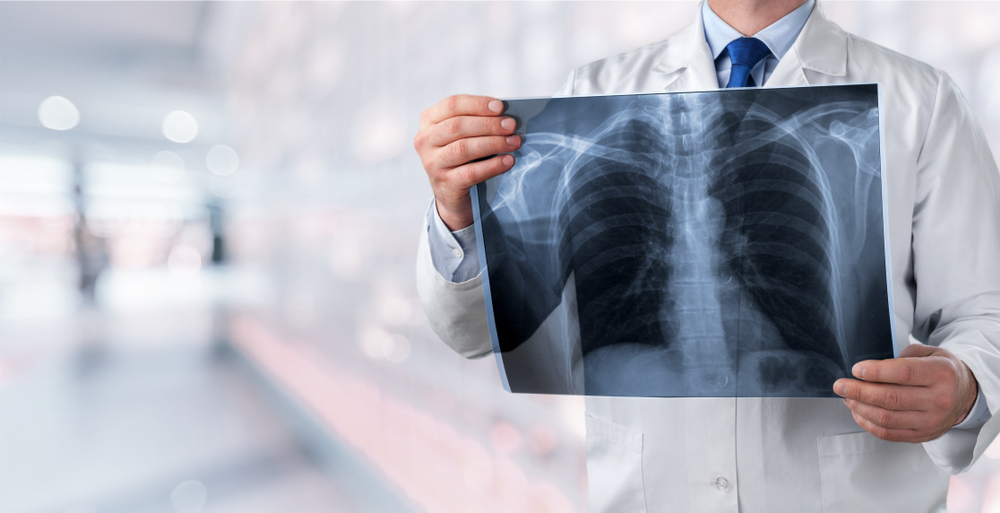

១. ជំងឺមហារីកសួត

ទោះបីជាការជក់បារីជាមូលហេតុចម្បងដែលធ្វើឲ្យកើតជំងឺមហារីកសួតក៏ដោយ អ្នកដែលស្រូបយកផ្សែងបារីក៏ទទួលផលប៉ះពាល់ដូចគ្នា។ ម្យ៉ាងវិញទៀត ជំងឺមហារីកសួតអាចបណ្ដាលមកពីការបំពុលបរិស្ថាន ប្រើប្រាស់ថ្នាំជក់ និងការប៉ះពាល់នឹងសារធាតុបង្កជំងឺមហារីក។ អ្នកដែលមានវ័យលើសពី៦០ឆ្នាំ និងធ្លាប់កើតជំងឺស្ទះផ្លូវដង្ហើមរ៉ាំរ៉ៃ ក៏អាចវិវដ្តទៅជាជំងឺមហារីកមួយប្រភេទនេះដែរ។

រោគសញ្ញា

នៅដំណាក់កាលដំបូង ជំងឺមហារីកសួតមិនបង្ហាញរោគសញ្ញាច្បាស់លាស់ក៏ពិតមែន ប៉ុន្តែគ្នាយើងអាចសង្កេតមើលសញ្ញាទាំងនេះ។

- ក្អក

- ដកដង្ហើមខ្លីៗ

- ស្អក

- ឈឺទ្រូង

- ដកដង្ហើមលឺខ្លាំងៗ

- កំហាកប្រែប្រួល

វិធានការការពារ៖ បញ្ឈប់ការជក់បារី និងនៅឲ្យឆ្ងាយពីផ្សែងបារី។